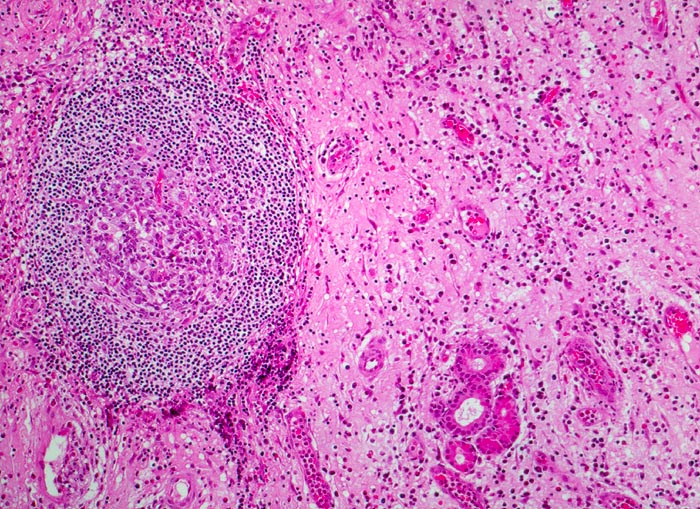

• Ödematöses Stroma mit gemischtem Entzündungsinfiltrat: Lymphozyten, Plasmazellen, Histiozyten und zahlreiche eosinophile Granulozyten.

• Im Zentrum des Polypen Drüsenläppchen und zahlreiche Blutgefässe.